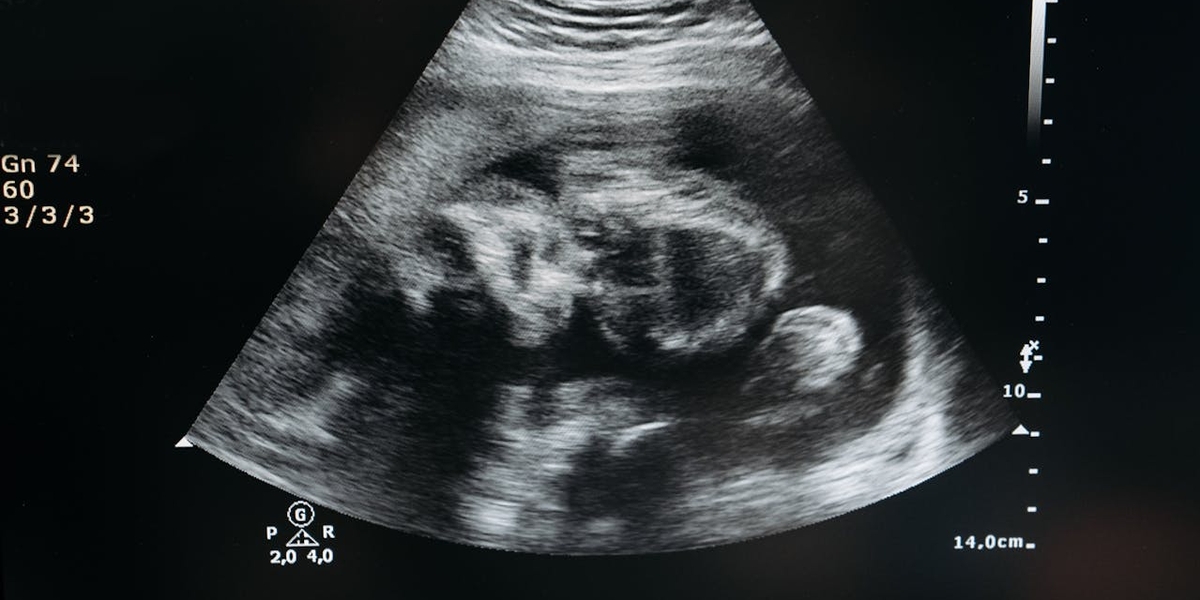

A Câmara dos Representantes de Porto Rico aprovou um projeto de lei que reconhece a criança ainda no ventre como pessoa natural no Código Civil.

A nova legislação estabelece que o ser humano em desenvolvimento no útero – em qualquer fase da gestação – passa a ser reconhecido legalmente como “pessoa natural”.